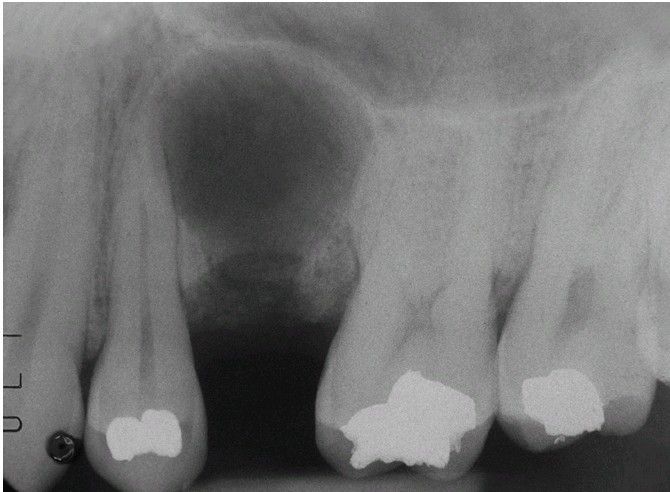

Residual Periapical Cyst

. Well-circumscribed radiolucency of the maxilla at the site of previous tooth extraction